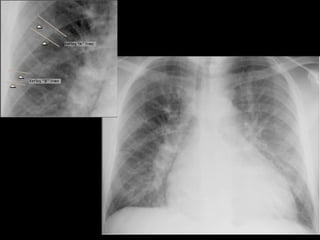

PROYECCIÓN POSTEROANTERIOR Necesita ser: De pie De 1.8 a 2 m de distancia Inspiraci ó n profunda Abatir los omoplatos

PROYECCIÓN POSTEROANTERIOR BORDE DERECHO Vena Cava Superior Aurícula Derecha BORDE IZQUIERDO  Botón Aórtico Arco de la Pulmonar Ventrículo Izquierdo

CARDIOMEGALIA  Mayor de 0.5 es sugestivo de cardiomegalia.  Índice Cardiotorácico   ICT =  A + B ________  C C B A

Factores que modifican el tamaño aparente de la silueta cardiovascular: Espiración Proyección Anteroposterior Ascitis Obesidad Embarazo Deformidades de la caja torácica